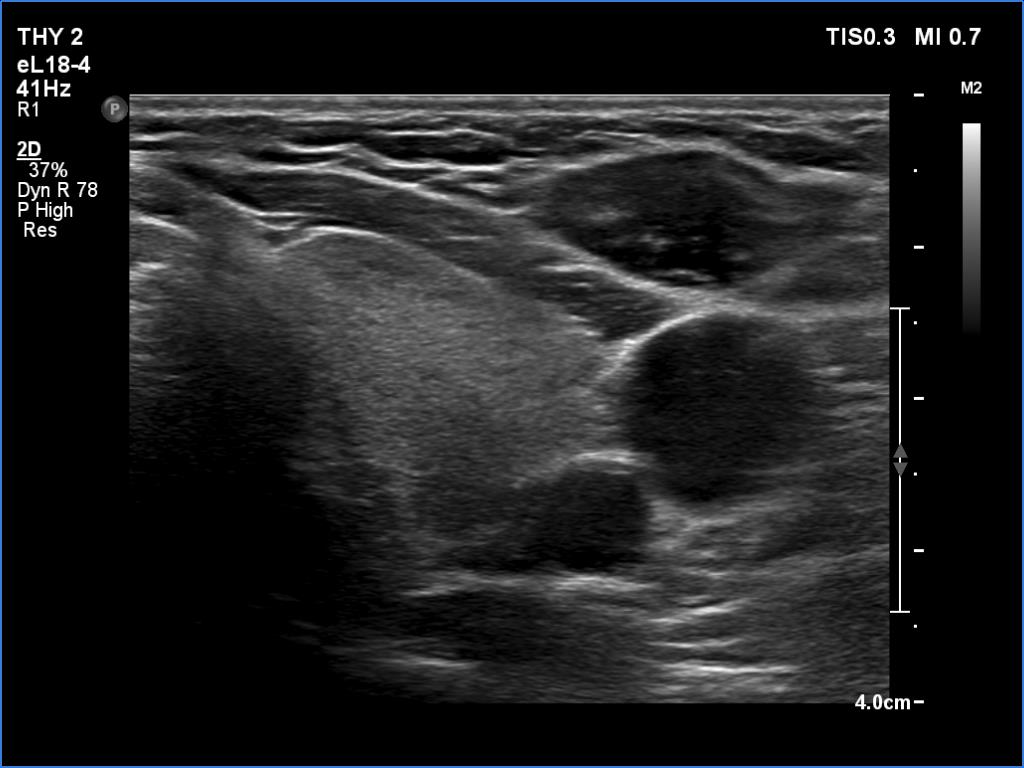

Lymphocytic thyroiditis - case 325 (ultrasonographic picture 9)

Left lobe, transverse scan. This lobe also has discrete areas.